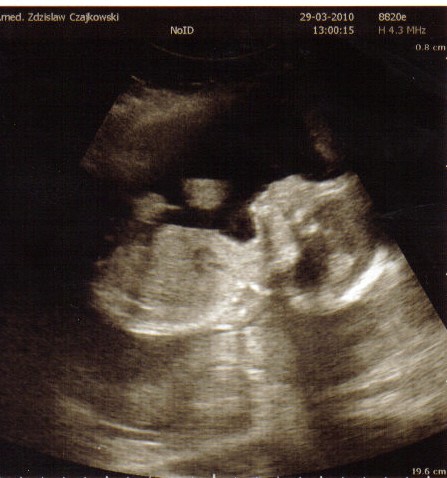

Zobacz załącznik 230489

Zdjęcie do góry nogami , bo i niunia była do góry nogami